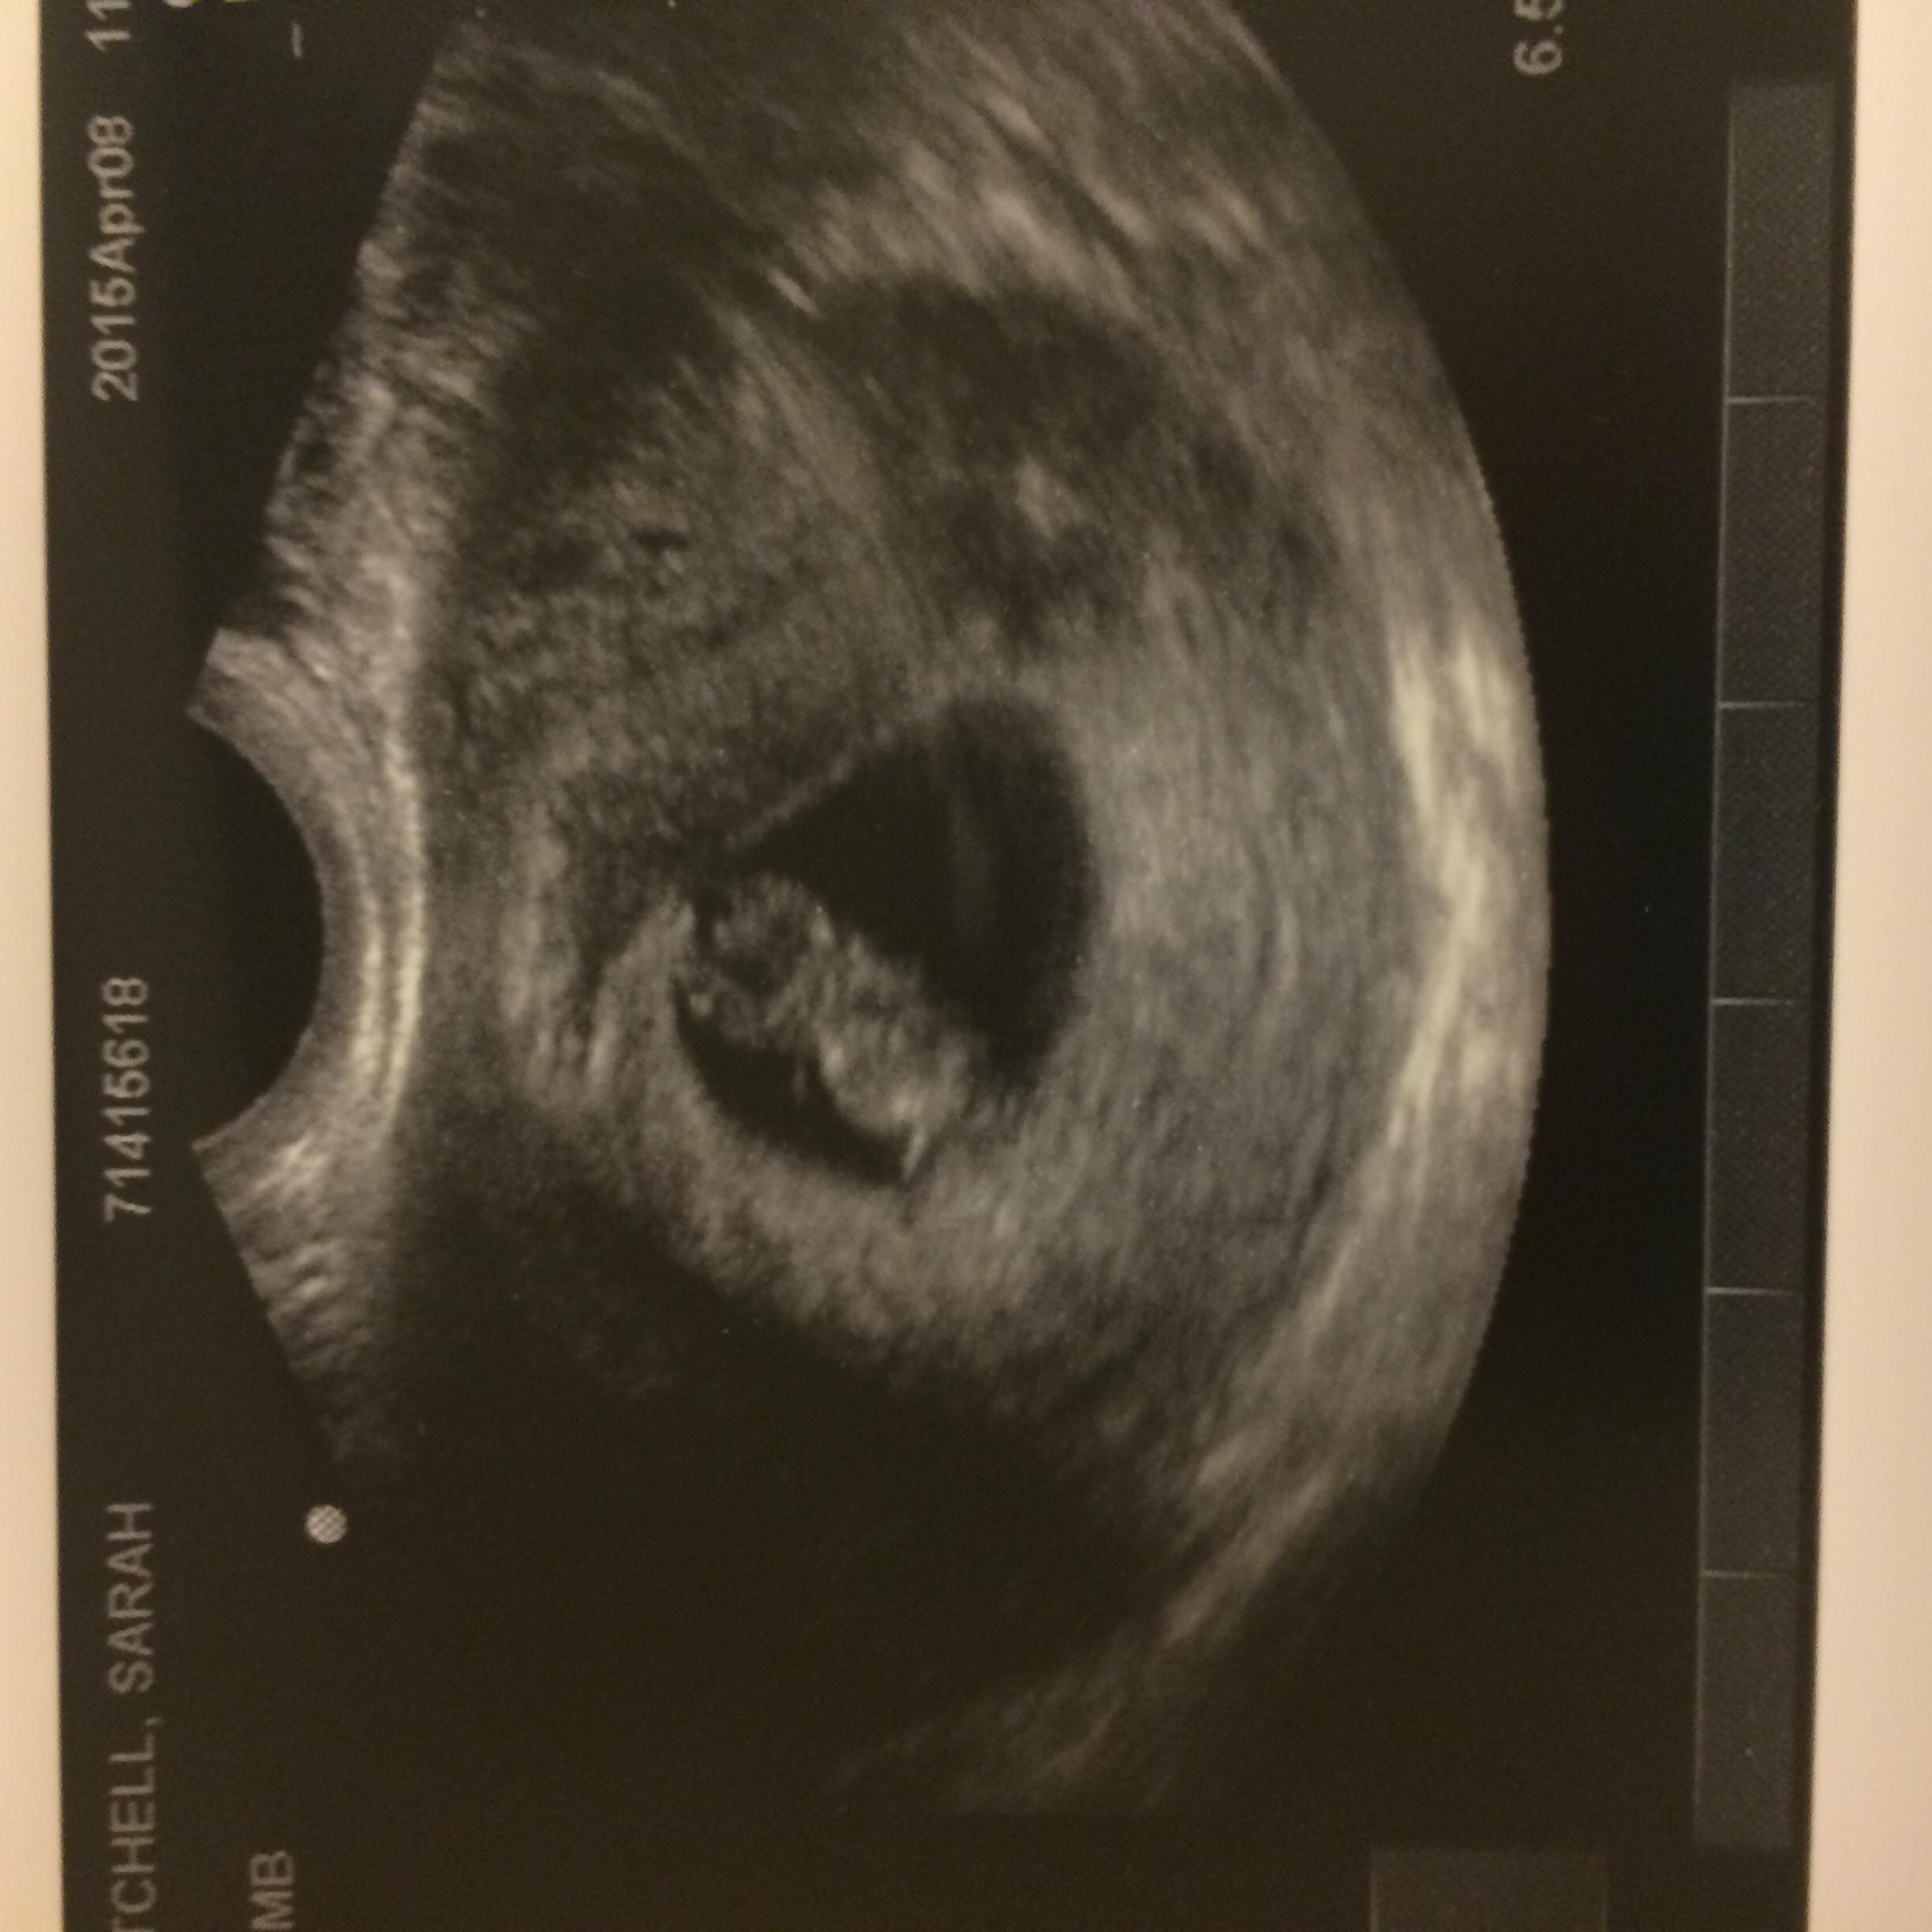

This was taken at exactly 8 weeks! Which was April 7th. I was so happy to see a little baby because when my pregnancy first started we thought I was farther along than I was so when I got an ultrasound it was just a sac which was very scary at the time.